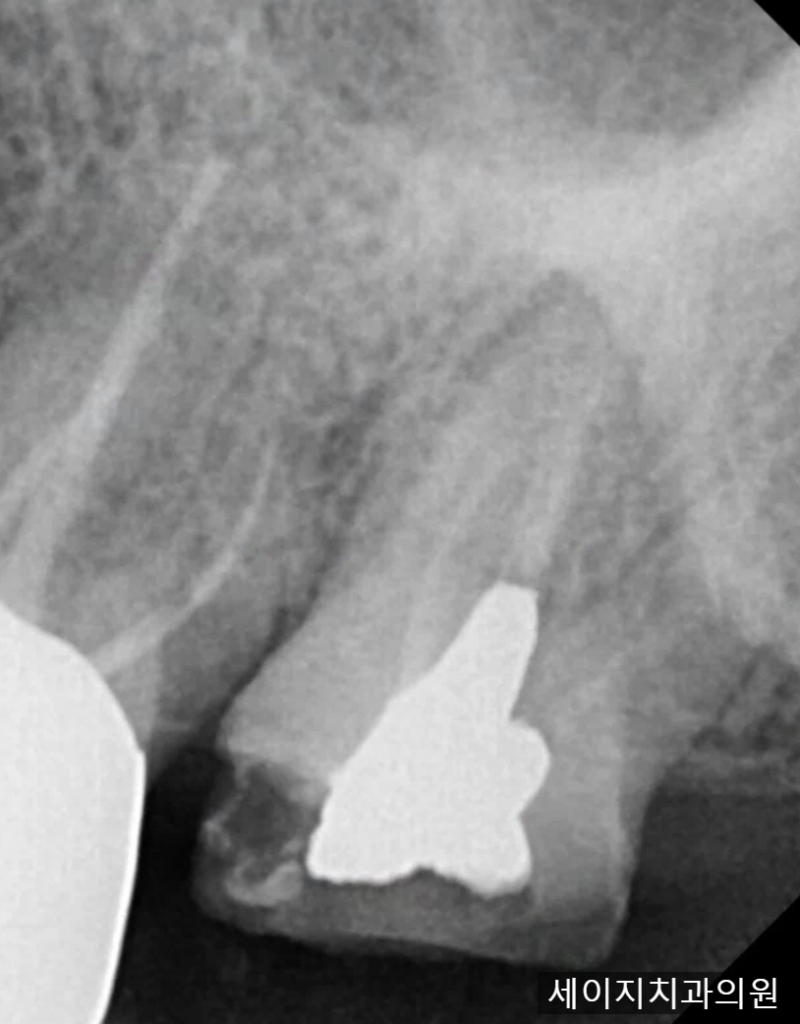

2024.04.16(기존 수복물이 탈락한 치아, 이차우식이 심한 상태)

맨끝 치아의 기존 크라운이 탈락하였는데, 크라운 내부에 있었던 재료까지 함께 탈락한 상황이었습니다.

2024.04.16(크라운이 떨어지면서 기존 치아도 같이 부러진 상황)

기존 크라운이 탈락하면서 크라운과 함께 안쪽 자연치아까지 함께 부서진 상황이었습니다. 크라운을 씌우신지는 기억이 나지 않을 정도로 오래되었다고 이야기 하셨으며, 평소 어금니 주변으로 음식물이 많이 끼어 불편하셨는데, 식사를 하다가 갑자기 치아가 부러져 나왔다고 이야기 하셨습니다.

치아의 내면을 살펴보니 이차우식이 존재하였고, ,충치를 제거하면 남아 있는 건전 치질의 양이 적어지기에 여러가지의 방법을 생각해 보았습니다.

2024.04.16(포스트와 레진코어를 이용하여 상실된 치아를 복구한 사진)

해당 치아는 잇몸과 잇몸뼈 사이의 공간을 이용한다면 2mm이상의 ferrule 효과를 얻을 수 있을 것으로 판단되었고 치아 내부의 충치 제거 후 Post 라는 기둥을 식립하고 레진 재료를 얹어 치아를 보강하였습니다.한주 정도 잇몸이 아무는시기를 거치며 환자분의 불편감이 생기지 않는지 관찰하기로 계획하였습니다.

포스트와 레진코어를 이용하여 상실된 치아를 복구한 사진 치아를 보강하여, 기존의 치아 외형을 복원하였고 크라운을 씌우기 적합한 Ferrule 효과도 부여하여 치아가 단단하게 기능을 할 수 있도록 만들었습니다.